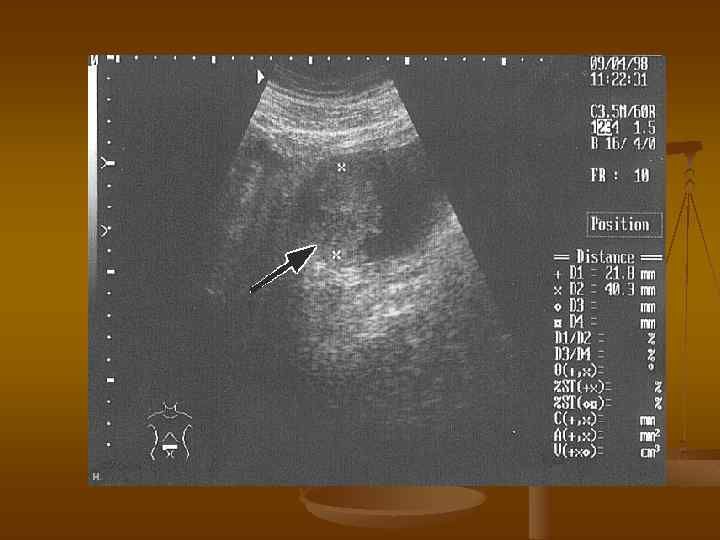

УЗИ n n n ультразвуковое исследование позволяет выявить экзофитные новообразования мочевого пузыря позволяет оценить степень опухолевой инфильтрации стенки мочевого пузыря и окружающих тканей и органов позволяет оценить состояние регионарных и парааортальных лимфатических узлов, почек, печени Диагностическая точность ультразвукового метода составляет 60 -70%